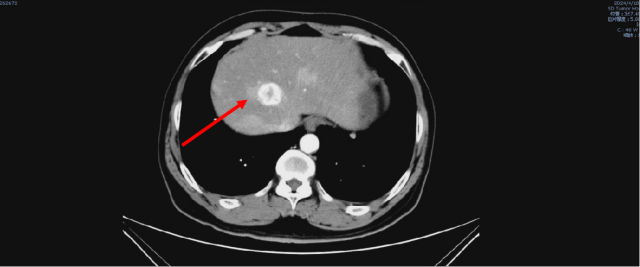

舒尼替尼治疗后,2024-04-17 复查CT

1. 结合临床,左肾癌术后;肝转移,较前(2023-05-09)进展;双肺转移,较前新发。

2. 右肺下叶少许炎症,较前变化不著。

3. 前列腺钙化灶;盆腔少量积液。

4. L5 双侧椎弓崩解;L2 椎体致密灶,变化不著,观察。